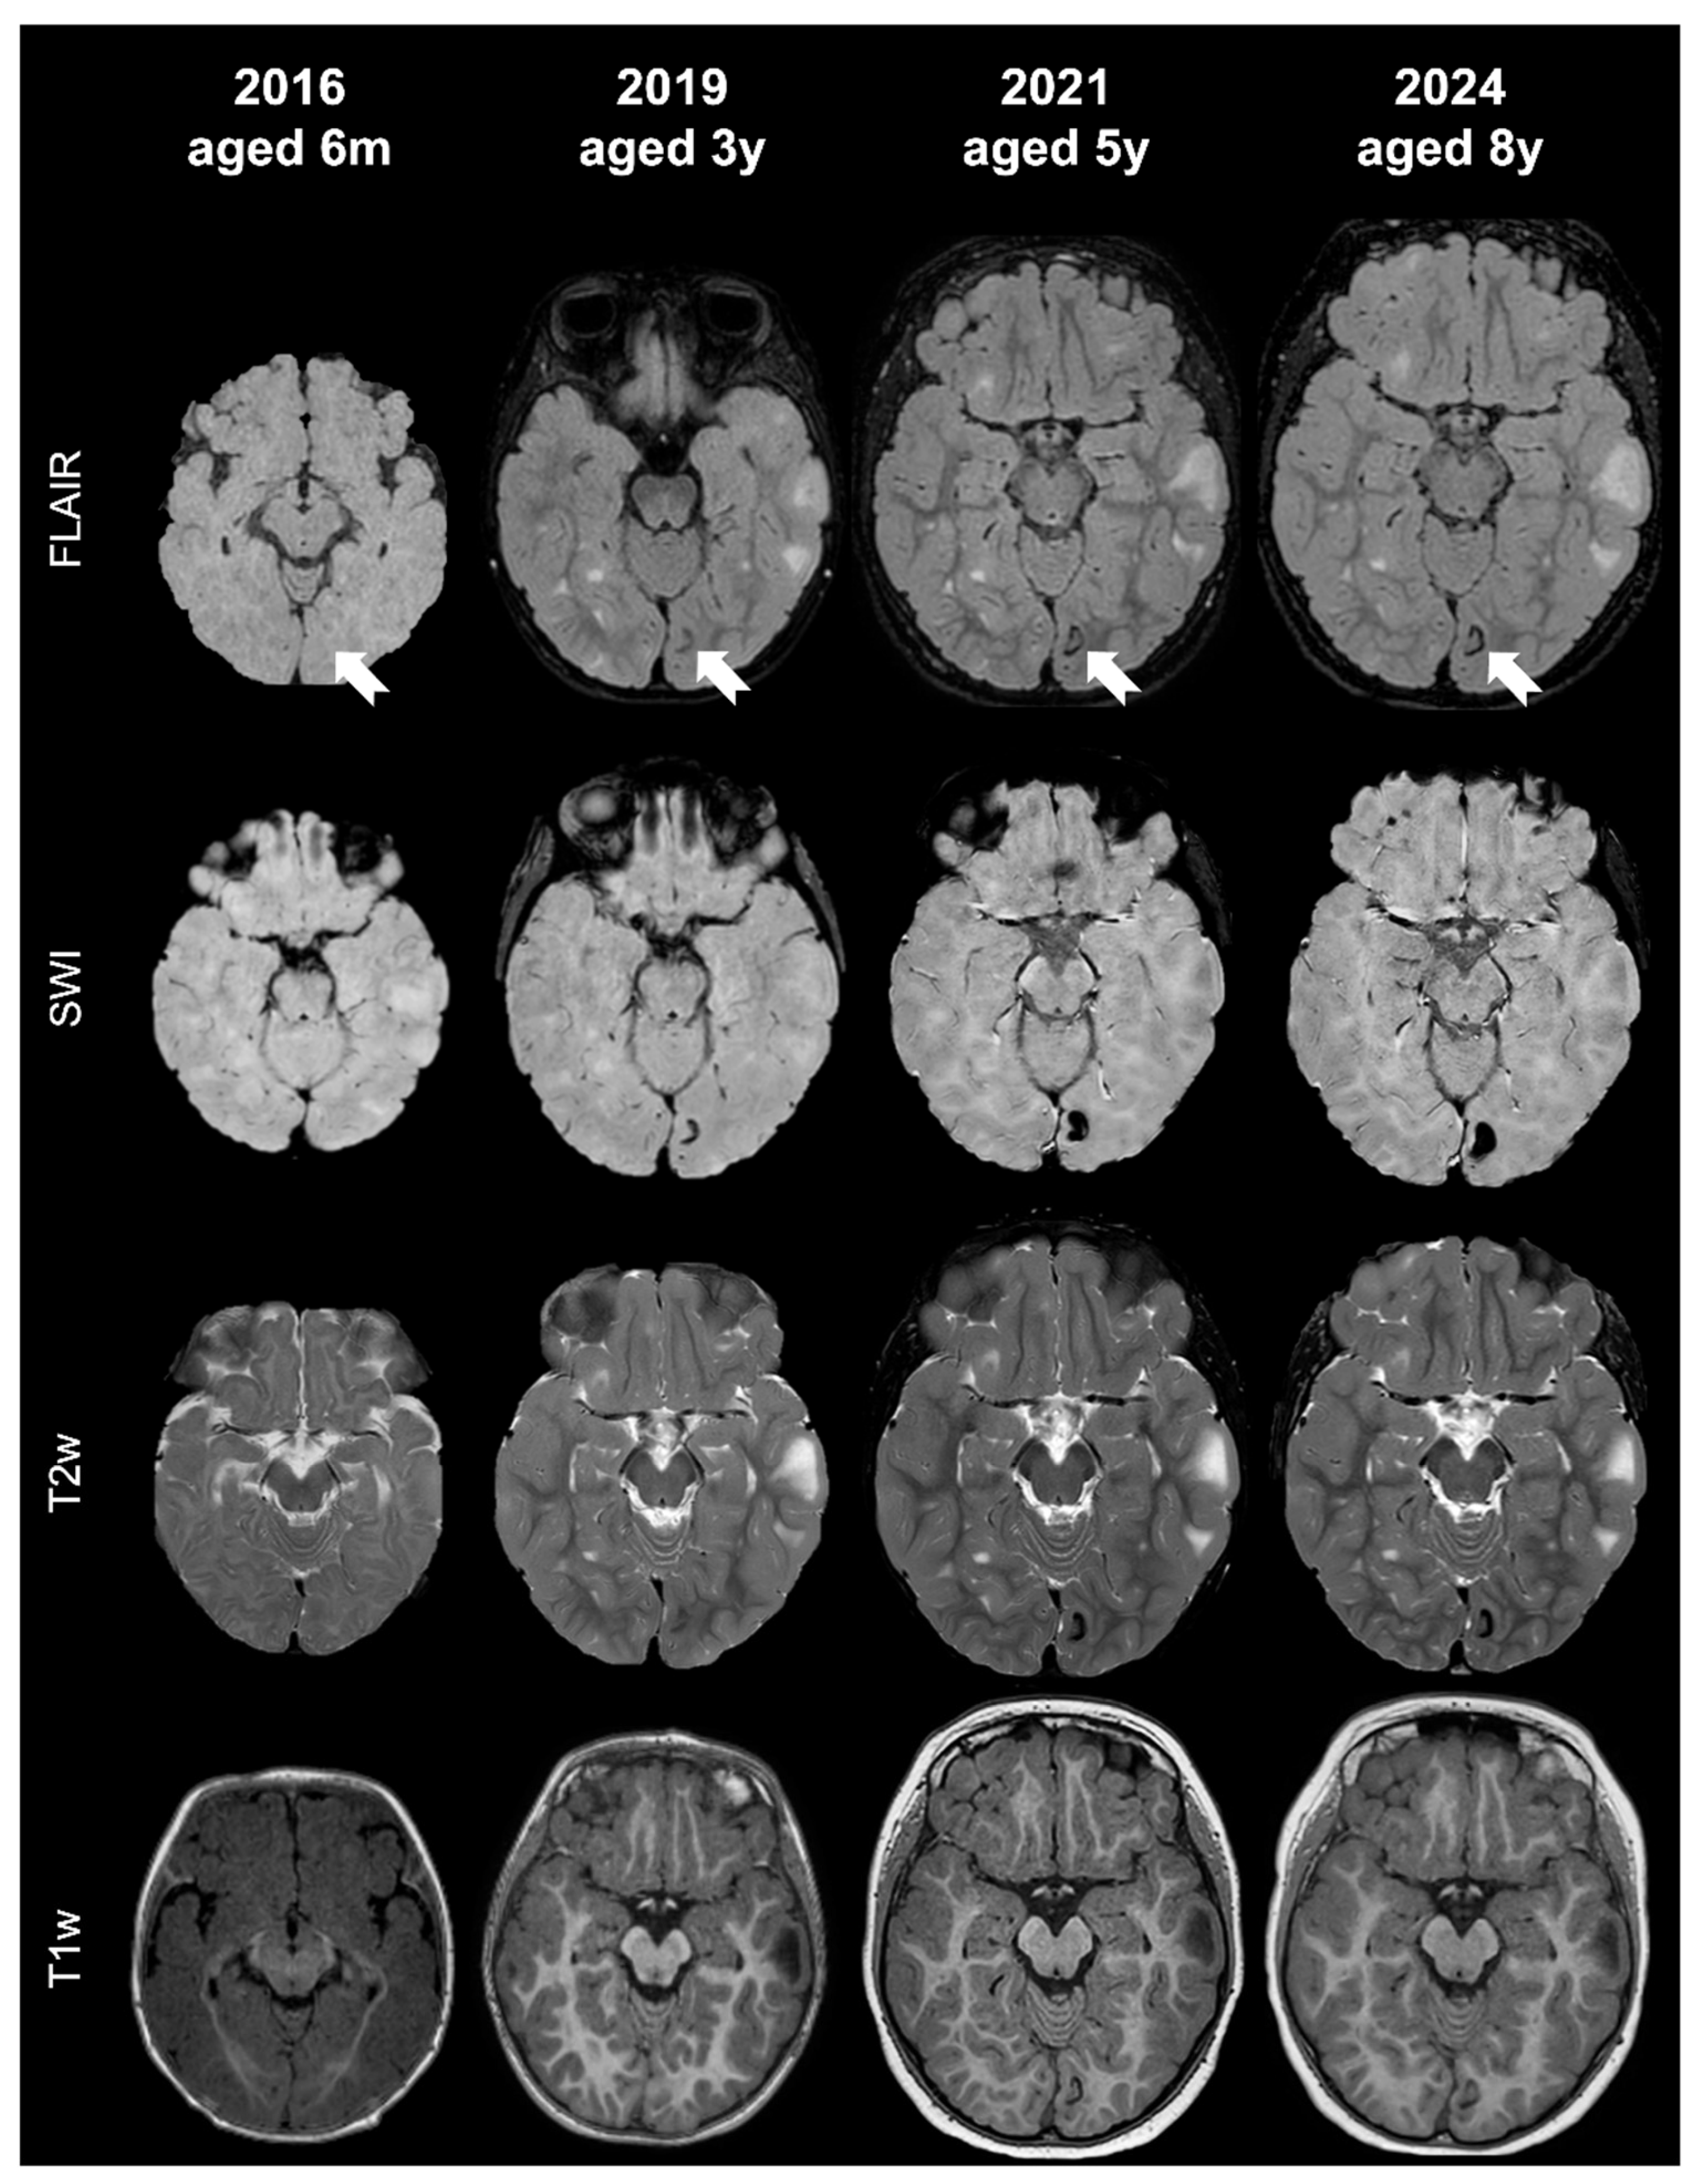

- Tuber A (corresponding to former tuber A in the classification by Gallagher et al., 2010 [27]): isointense on volumetric T1-weighted images and subtly hyperintense on T2-weighted images, with no mass effect, no distortion of the gyral folding pattern, and no calcifications on SWI.

- Tuber B (corresponding to former tuber B in the classification by Gallagher et al., 2010 [27]): hypointense on volumetric T1-weighted images and homogeneously hyperintense on T2-weighted images, with no well-defined borders, minimal mass effect, slight disruption of the gyral pattern, and no calcifications on SWI.

- Tuber C: hypointense on volumetric T1-weighted images and homogeneously hyperintense on T2-weighted images with inner calcifications on SWI, further divided into the following:

- Tuber D: hypointense on volumetric T1-weighted images and homogeneously hyperintense on T2-weighted images with a central cystic area of vacuolization, regardless of the presence of associate calcification(s).

- Tuber A: isointense on volumetric T1-weighted images and subtly hyperintense on T2-weighted images, with no mass effect, no distortion of the gyral folding pattern, and no calcifications on SWI

- Tuber B: hypointense on volumetric T1-weighted images and homogeneously hyperintense on T2-weighted images, with no well-defined borders, minimal mass effect, slight disruption of the gyral pattern, and no calcifications on SWI

- Tuber C1: with subtle, non-confluent, pinpoint-like calcifications on SWI (micro-calcified)

- Tuber C2: with large, confluent, linear or curvilinear calcifications on SWI (macro-calcified)

- Tuber D: hypointense on volumetric T1-weighted images and homogeneously hyperintense on T2-weighted images, with a central cystic area of vacuolization, regardless of associated calcification(s).